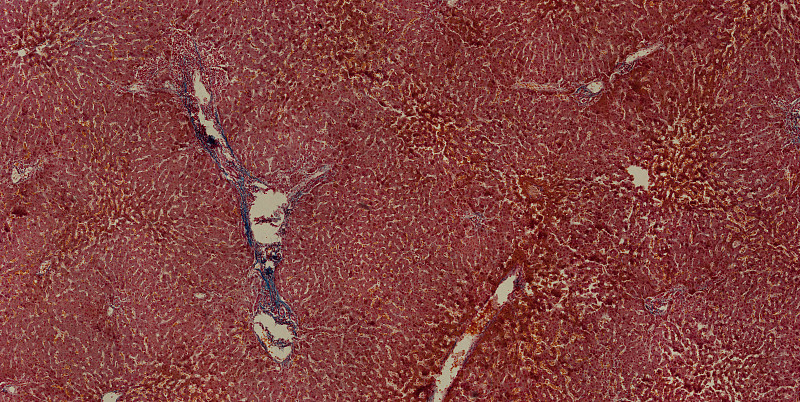

显微镜下的人肝细胞详情

JPG